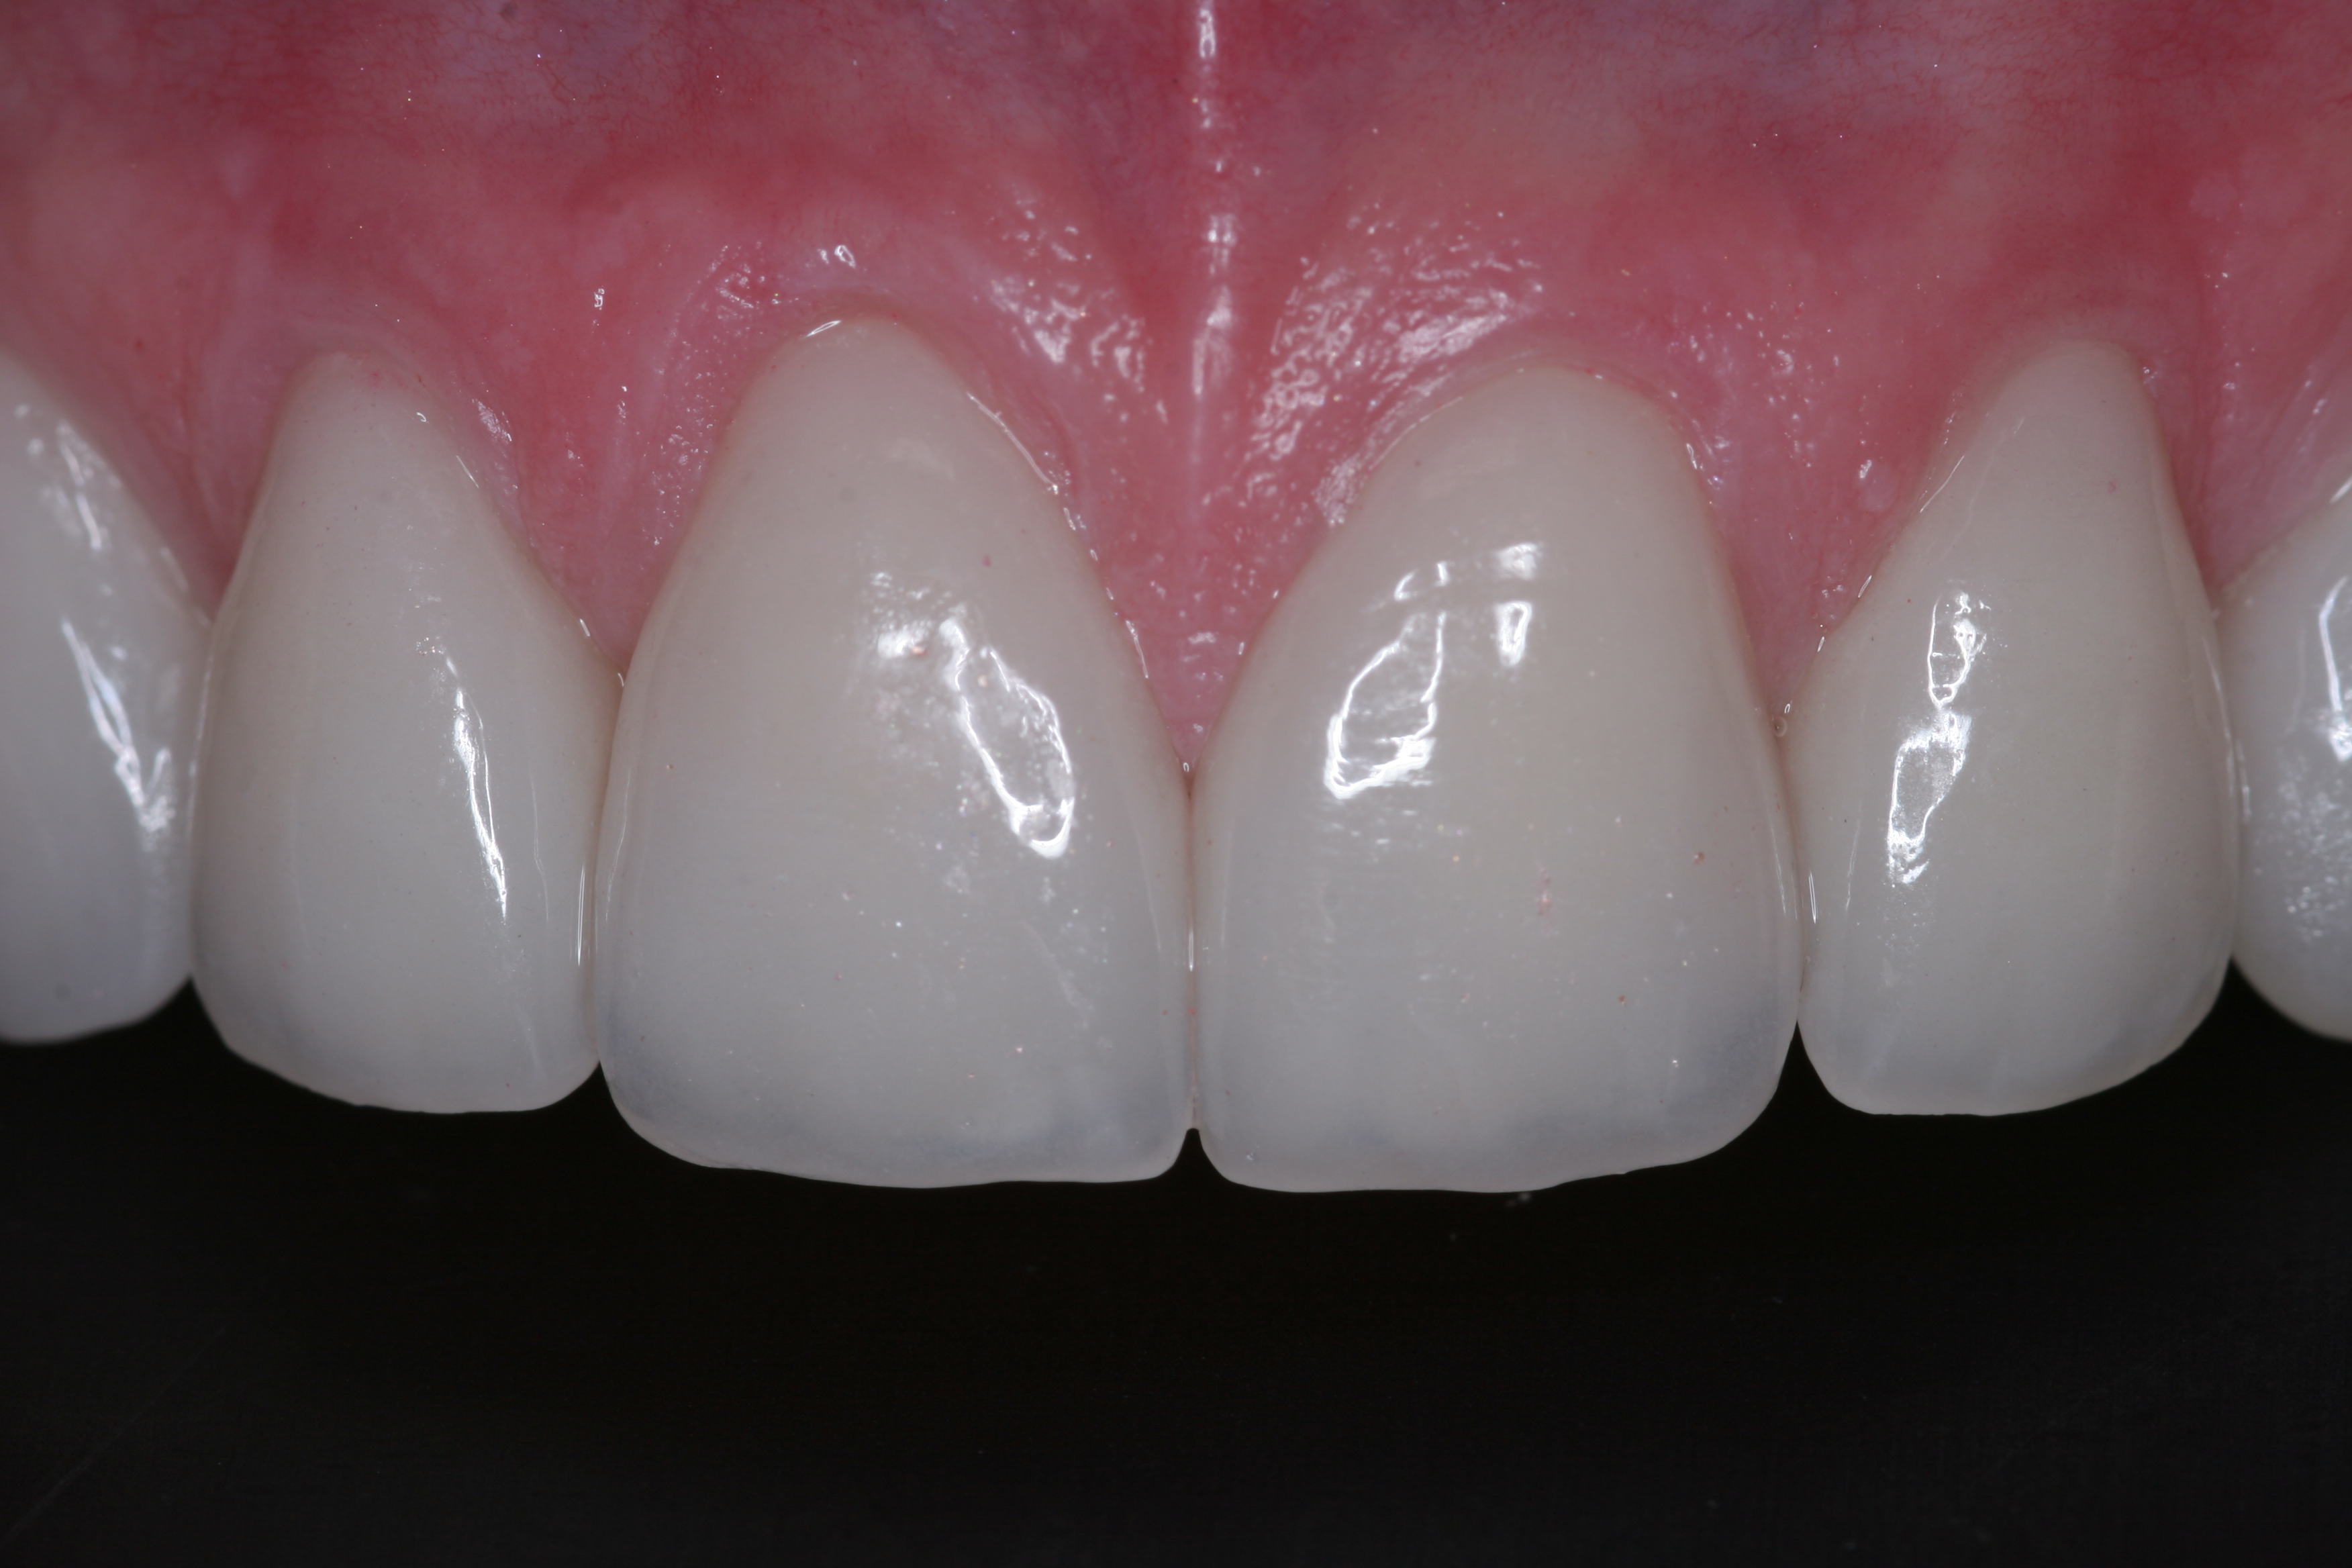

(22.) The final restorations, which reflect the changes modeled through the provisional phase.

Figure 22

(23.) The final restorations, which reflect the changes modeled through the provisional phase.

Figure 23

(24.) The final restorations, which reflect the changes modeled through the provisional phase.

Figure 24

Once approved, impressions of the provisionals were taken so the laboratory could precisely copy the 3D position of the anterior teeth as successfully proven in the provisionals. The postoperative result and final functional photographs are shown in Figure 22 through Figure 29. Posterior treatment can now be completed in segments as necessary. Posterior morphology will be developed in harmony with the now corrected anterior contour and functional parameters. The fulfillment of the previously mentioned requirements of occlusal stability were evaluated and refined in the final restorations. The patient was placed in a posttreatment dual-arch B splint appliance to help manage any further parafunctional forces should they occur.